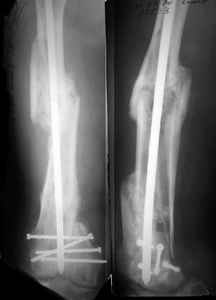

THX, initial images are

1,

2.

At that moment we had in stock only the 10 mm solid nails so of course there was no idea about early weight bearing. But it was quite enough for early knee ROM excersises (see attached). Two locking screws through the distal block provided that.